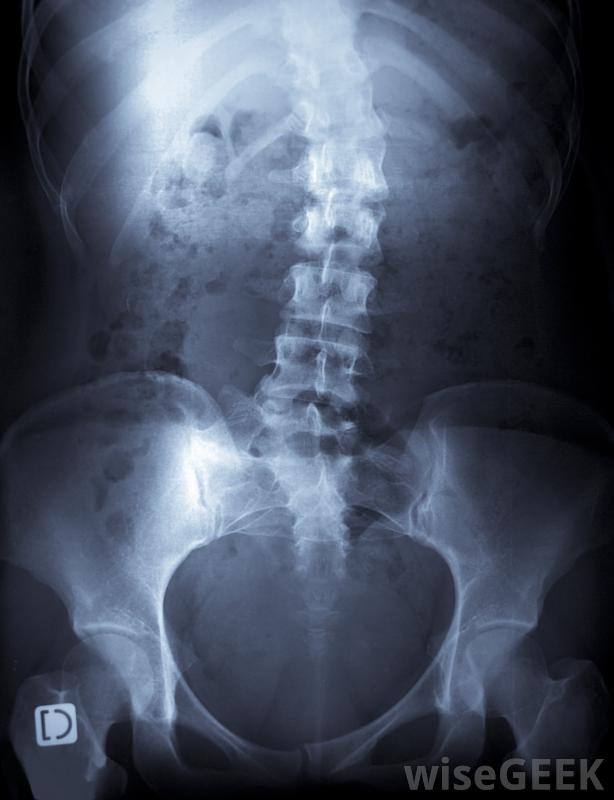

普拉提是约瑟夫·普拉提(Joseph Pilates)的创意,最初的目的是为受伤的士兵提供一个无障碍的锻炼计划。它提供全身调节,重点关注核心肌肉——尤其是背部、骨盆和腹部。现在,普拉提已成为全世界健身活动的一部分,普拉提被认为可以缓解许多身体和健康状况,包括脊柱侧凸。脊柱侧凸运动的特定普拉提可以减轻脊柱弯曲的不适,在某些情况下,有助于减轻曲线的严重程度。

在某些情况下,使用普拉提治疗脊柱侧凸可以减轻曲线的严重程度。并不是所有的专家意见都支持使用普拉提来治疗脊柱侧凸以减轻这种症状和体征。一些人认为脊柱侧凸通常是由遗传倾向引起的。这些人认为脊柱侧凸本质上是由脊柱侧凸引起的由于神经系统发育不全,因此很少能通过努力改善姿势和运动模式来纠正。这一学派通常反对使用普拉提治疗脊柱侧凸,相信某些体位甚至会加重病情。